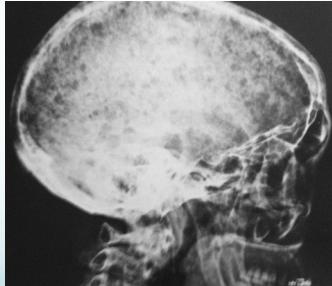

Radiological Features

- X-ray:

- Multiple punched-out lesions

- Osteoporosis & Vertebral compression fracture:

- If both present in a male >45: ? Myeloma

- Common sites:

- Skull, Prox. Femur, vertebrae